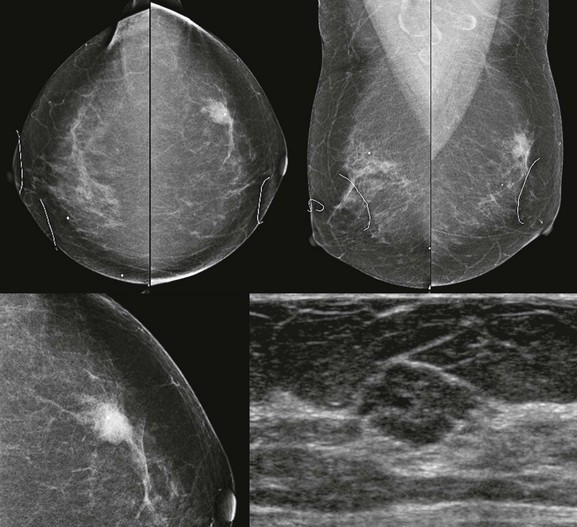

FIGURE 11-3 Shrinking Breast.

A 52-year-old woman noted thickening in her left breast. On clinical examination, the breasts are symmetric in size but the texture of the left breast is diffusely thickened. On mammography, the left breast appears to be smaller than the right. Biopsy showed ILC. Did you also notice the one-view asymmetry in the right medial breast? US of this area shows a small hypoechoic mass. Biopsy of the right breast showed IDC.

On US, ILC may present as a defined mass (see Fig. 11-3) but more often presents as ill-defined areas of shadowing without a distinct mass (see Fig. 11-2). The lines and arcs of tumor can produce bands of shadowing, like the edges of a spider web. Although tumor size is often underestimated by US, this modality is more accurate than clinical examination or mammography in assessing extent of disease.